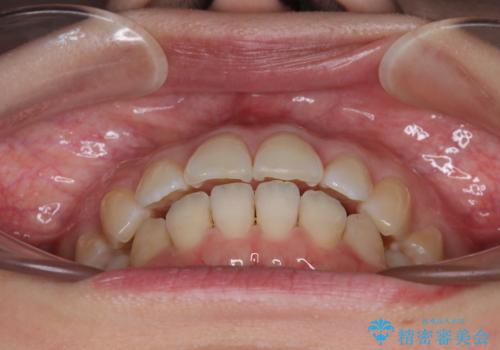

- 上下前歯の後戻りを気にして来院された患者様です。

インビザラインでの治療を希望されていて、デコボコの程度が中等度であり、安価なパッケージにて対応可能と判断されたため、インビザライン・モデレートを用いて矯正治療を行うこととしました。